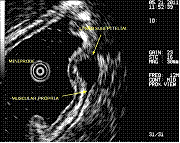

Por outro lado, a Ecoendoscopia permite também esclarecer se um determinado abaulamento da parede do tubo digestivo corresponde a uma compressão provocada por um órgão vizinho, ou a uma lesão da própria parede, camuflada, por uma mucosa de aspecto normal; neste caso, a Ecoendoscopia permite caracterizar essa lesão avaliando com precisão o seu tamanho, camada de origem na parede e diversas características morfológicas, podendo sugerir o diagnóstico mais provável. Em alguns doentes, poderão ser obtidas biópsias sob controlo ecográfico (punção-biópsia aspirativa com agulha fina) que complementam a investigação.